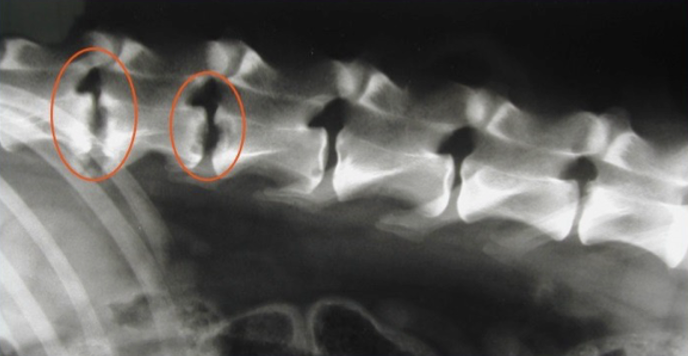

You have a dog presenting for non-head involved ataxia. Only the hindlimb are involved and there is pain. You take rads and this is what you see. What do you think it is? What is the treatment?

A

discospondylitis

8+ weeks Abx or antifungals (week 1 IV if neuro deficits), pain relief, cage rest